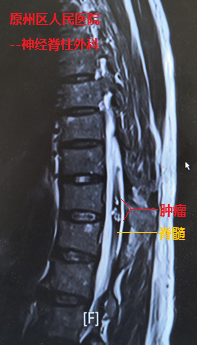

经检查发现,在史伯伯的胸椎脊髓内,长有信号混杂不均的血管性肿瘤,并随着肿瘤出血膨胀,几乎占据了整个脊髓,导致患者一侧下肢近远端肌力完全丧失(0级),另一侧下肢也仅能勉强移动(2-3级)。当地医院神经脊柱外科主任万欣龙判断,史伯伯得的可能是脊髓髓内的海绵状血管瘤并发出血卒中,如若不进行手术,随着肿瘤出血后脊髓水肿的加重,病情将进一步恶化。

我院神经外科援宁队员郑小斌在查看患者并详细阅片后,组织了疑难病例讨论,考虑到患者血管性肿瘤体积大,且生长时间长达十余年,导致该肿瘤与周围脊髓组织的血供情况复杂,最终决定采用显微镜下经脊髓外侧沟切开脊髓并暴露肿瘤。郑小斌介绍,术中对肿瘤与脊髓边界的分离是手术的关键,加上患者脊髓功能受损严重,手术操作既要精细轻柔,也需连贯稳定。经过近2个小时不间断的显微镜下操作,肿瘤顺利从脊髓内切除,周围的脊髓的正常结构得到保护。鉴于肿瘤体积大,出血后脊髓水肿严重,同期给予行脊柱椎板切除减压手术,并进行内固定手术加强脊柱的稳定性,手术顺利完成。

郑小斌博士介绍,该脊髓血管性肿瘤由于体积较大,并且生长时间久,瘤周及脊髓表面的血管出现反应性增生,寻找合适的脊髓切开位置并暴露肿瘤,同时保护好脊髓的正常血供与静脉引流系统,是显微镜下操作首先需要注意的。该血管性肿瘤呈分块状,除了需要高倍显微镜下的操作,如何在尽可能小的脊髓切开范围,全部摘除肿瘤,并保护好脊髓的血供与静脉引流系统,最大化保留脊髓的残存功能,是手术操作的原则。